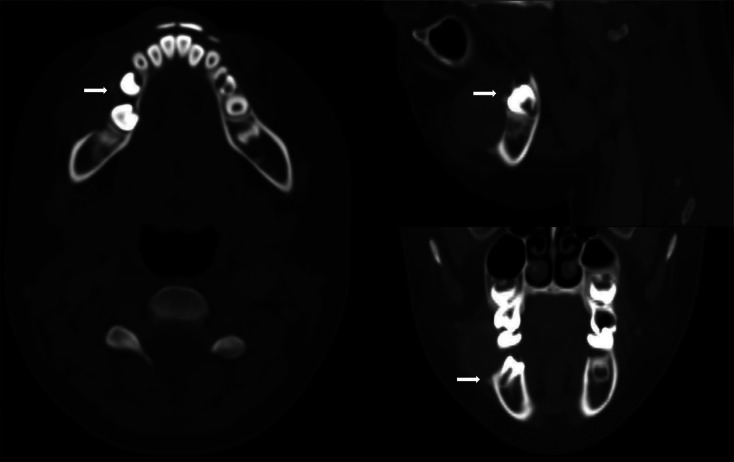

Teaching point: Peripheral giant cell granuloma (PGCG) is a common benign hyperplastic reactive lesion that originates from the soft tissues of the oral cavity and should be considered following a tooth extraction.

Abstract Image